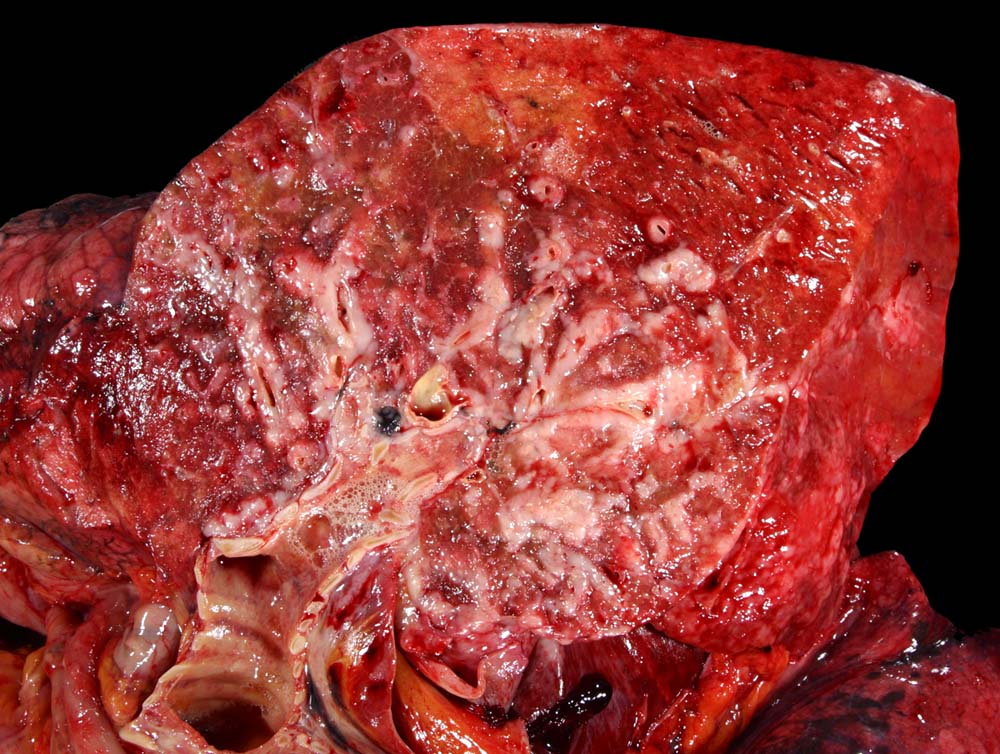

Das metastatische Wachstumsmuster von primären Bronchuskarzinomen und extrapulmonalen Tumoren innerhalb der Lunge ist variabel. Hämatogene Metastasen imponieren makroskopisch als multiple scharf begrenzte rundliche Knoten in allen Lappen meist in peripherer Lage. Der metastatische Befall von Lymphknoten kann durch direkte Tumorinfiltration durch den Primärtumor erfolgen (=per continuitatem) oder über die Lymphgefässe. Bei einer ausgeprägten lymphogenen Tumorausbreitung erscheinen subpleurale mit Tumor gefüllte Lymphgefässe makroskopisch als prominente weisse Streifen. Mikroskopisch lassen sich Tumorinfiltrate in peribronchialen und perivaskulären Lymphgefässen nachweisen (=Lymphangiosis carcinomatosa). Hepatozelluläre Karzinome metastasieren typischerweise in Form von Tumorembolien (> 1279) hämatogen in die Lunge.

• Sternförmiges Karzinom mit zentraler Vernarbung mit reichlich schwarzem Anthrakosepigment.